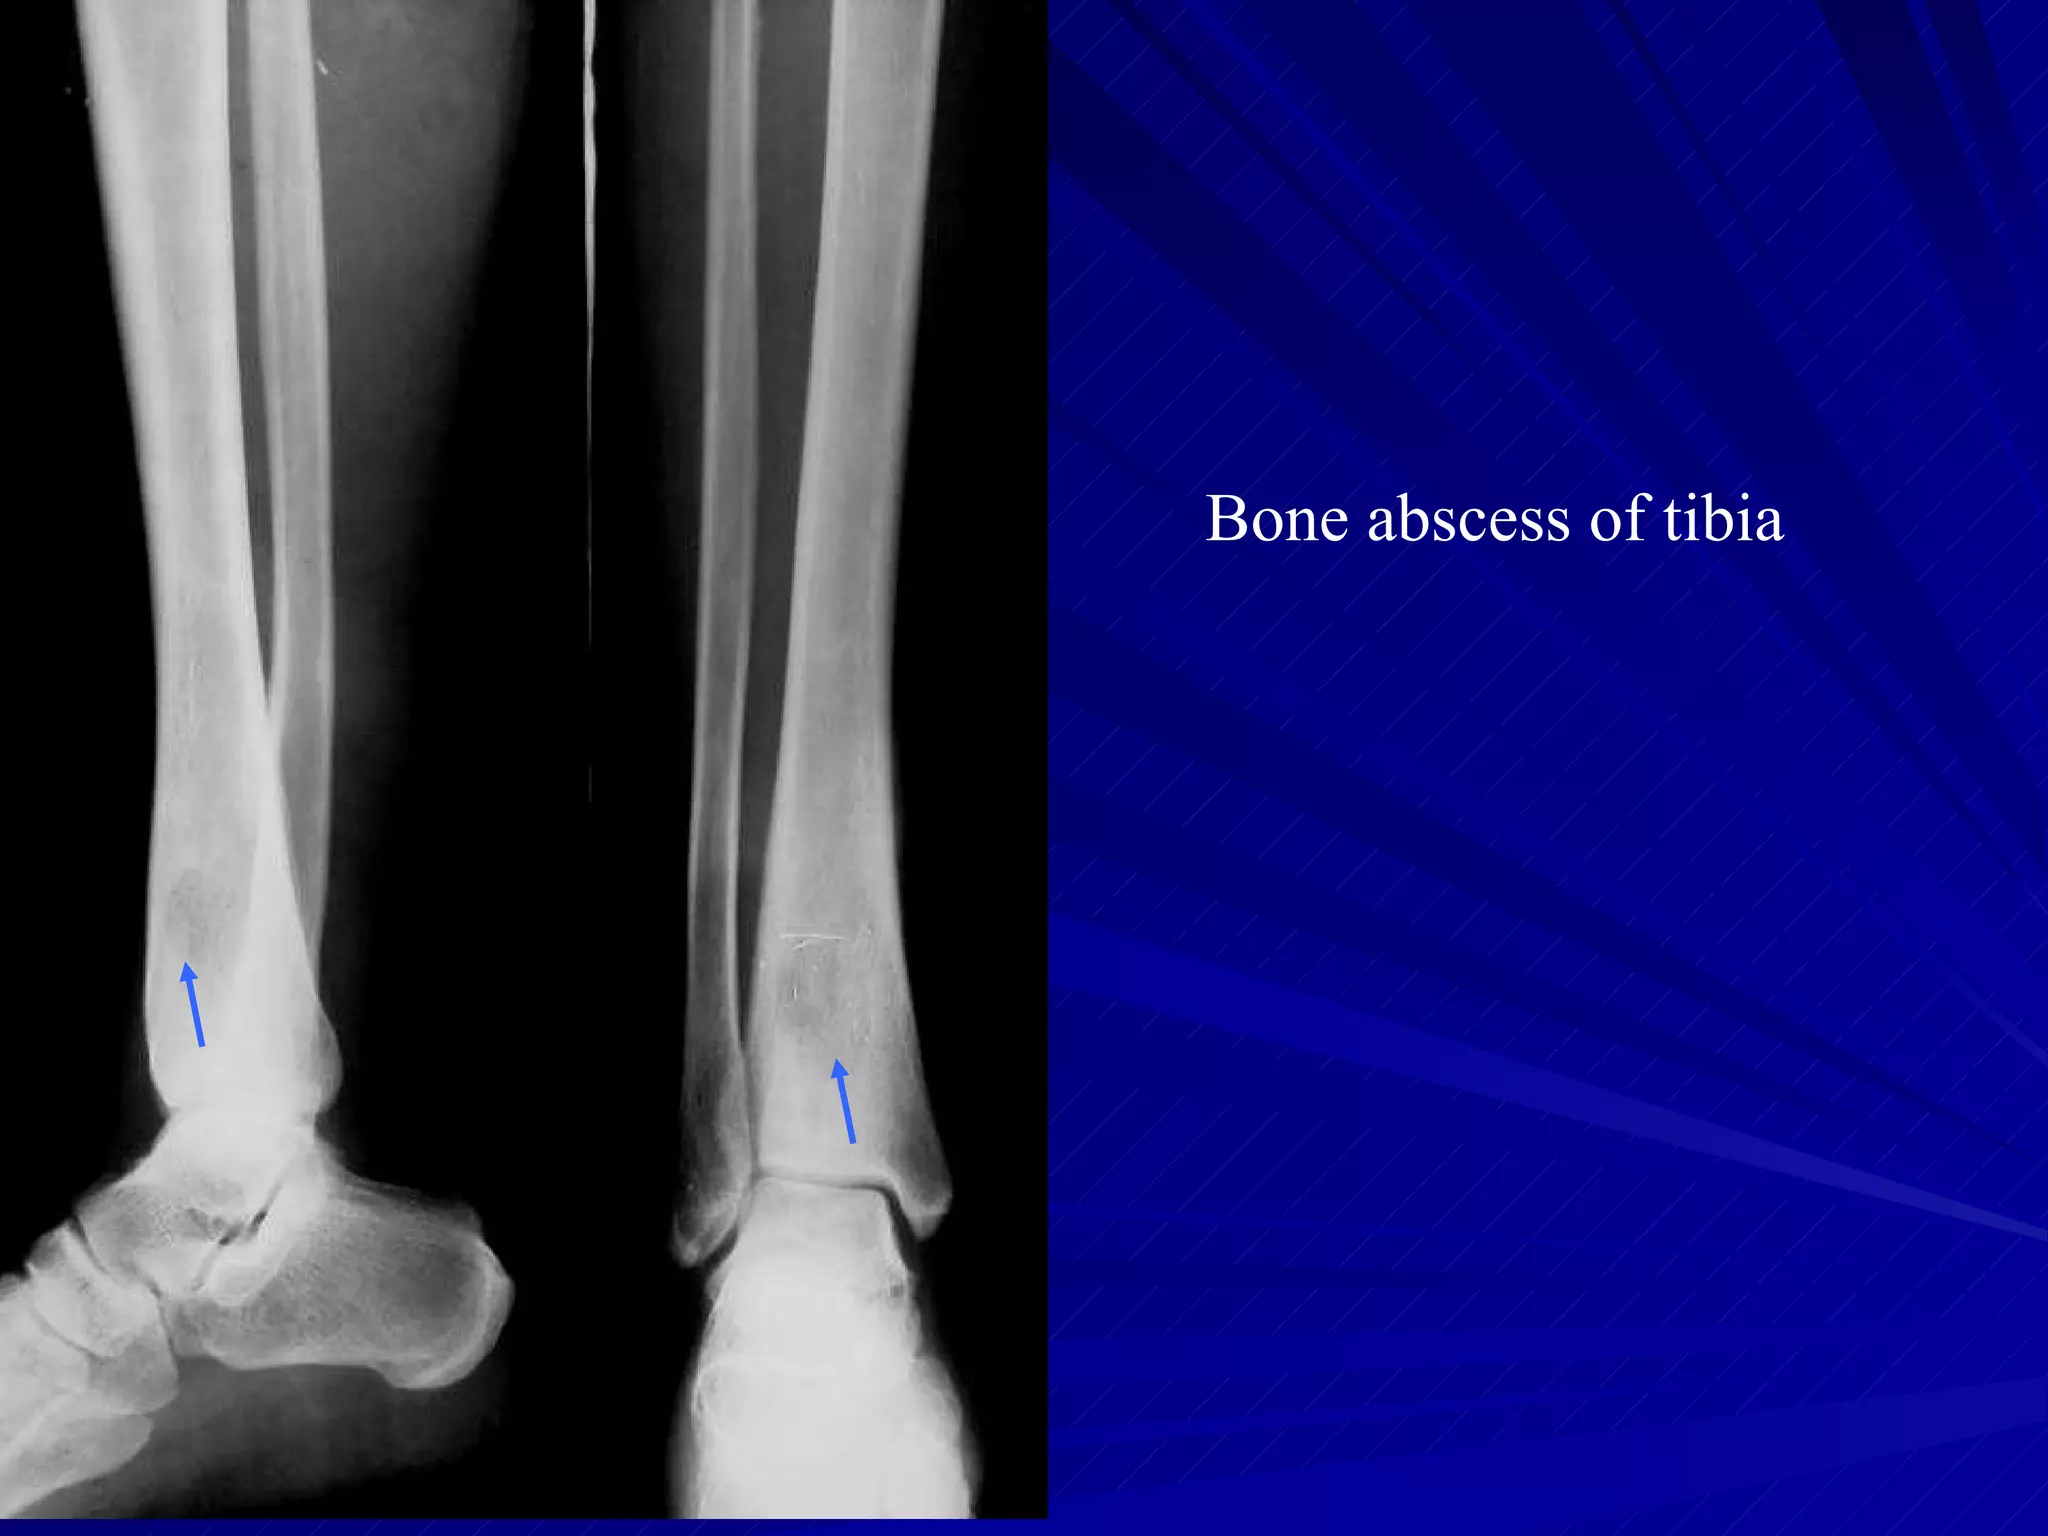

The document discusses various types of infectious diseases of bones and joints, including acute and chronic pyogenic osteomyelitis, Brodie's abscess, tuberculosis of long bones and the spine, and infectious arthritis. Specific examples provided include tuberculosis of the spine, hip, knee, and foot bones as well as pyogenic arthritis affecting the hip and knee joints. The document also mentions normal x-ray appearances of joints and basic features of joint diseases visible on x-rays such as swelling, destruction, degeneration, ankylosis, and dislocations.